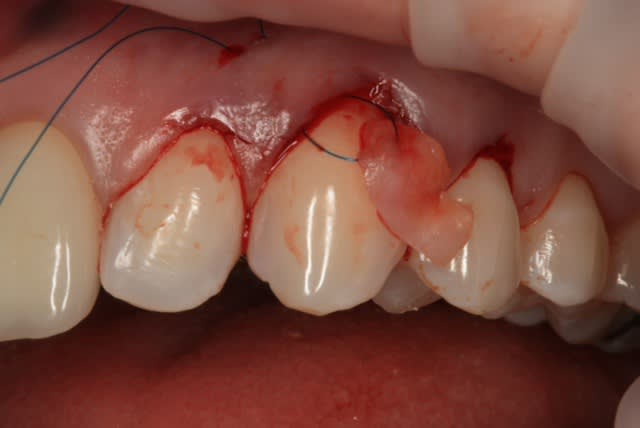

Comme on voit pas bcp de muco sur eugenol

P'tite 23 qui montrait trop de racine

Les 2 dernières photos sont à la dépose des fils (14 jours)